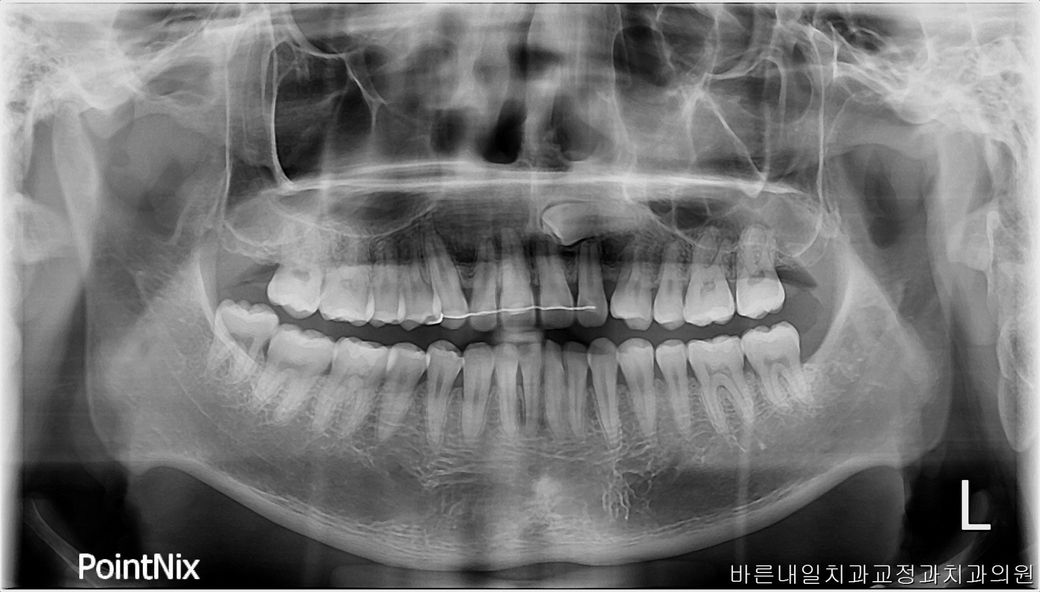

매복 송곳니 무시하고 교정 후 임플란트 되나요??

오늘 서울 모 대학병원을 가보니 매복니를 발치할 경우 높은 확률로 앞니가 신경이 죽는다네요… 혹시 이런경우 발치 없이 임플란트가 될까요?

정확한 위치관계는 ct를 찍어 3차원으로 확인해봐야 합니다만 파노라마 사진으로도 매복치가 정상 앞니의 뿌리에 근접하여 위치해 있긴 하네요

굳이 건드리지 않는 것이 좋을 수도 있습니다

그냥 매복 송곳니는 묻어두고, 교정으로 공간 확보 후 송곳니 부위 임플란트 심는 것을 고려해보시면 됩니다.